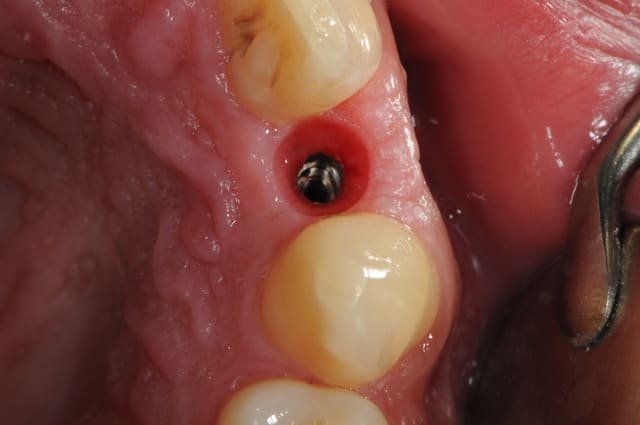

-cicatrisation

-mise en place vis de cica petit diamètre

-ensuite on augmente le diamètre en conservant et en gonflant les tissus gingivaux

-cicatrisation de la première vis de cica,

-diamètre plus gros pour la vis de cica